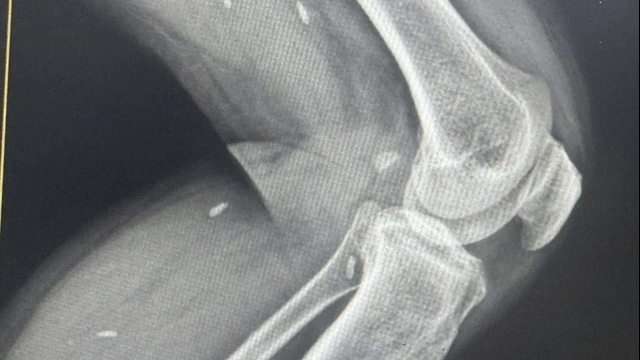

Cụ thể, trong số này có 1 trường hợp tử vong, 1 trường hợp nhảy từ tầng cao bị đa chấn thương đã được phẫu thuật ngay; 3 trường hợp bị thương nhẹ đã được ra viện. Như vậy, hiện cơ sở này đang điều trị, theo dõi 2 trường hợp.